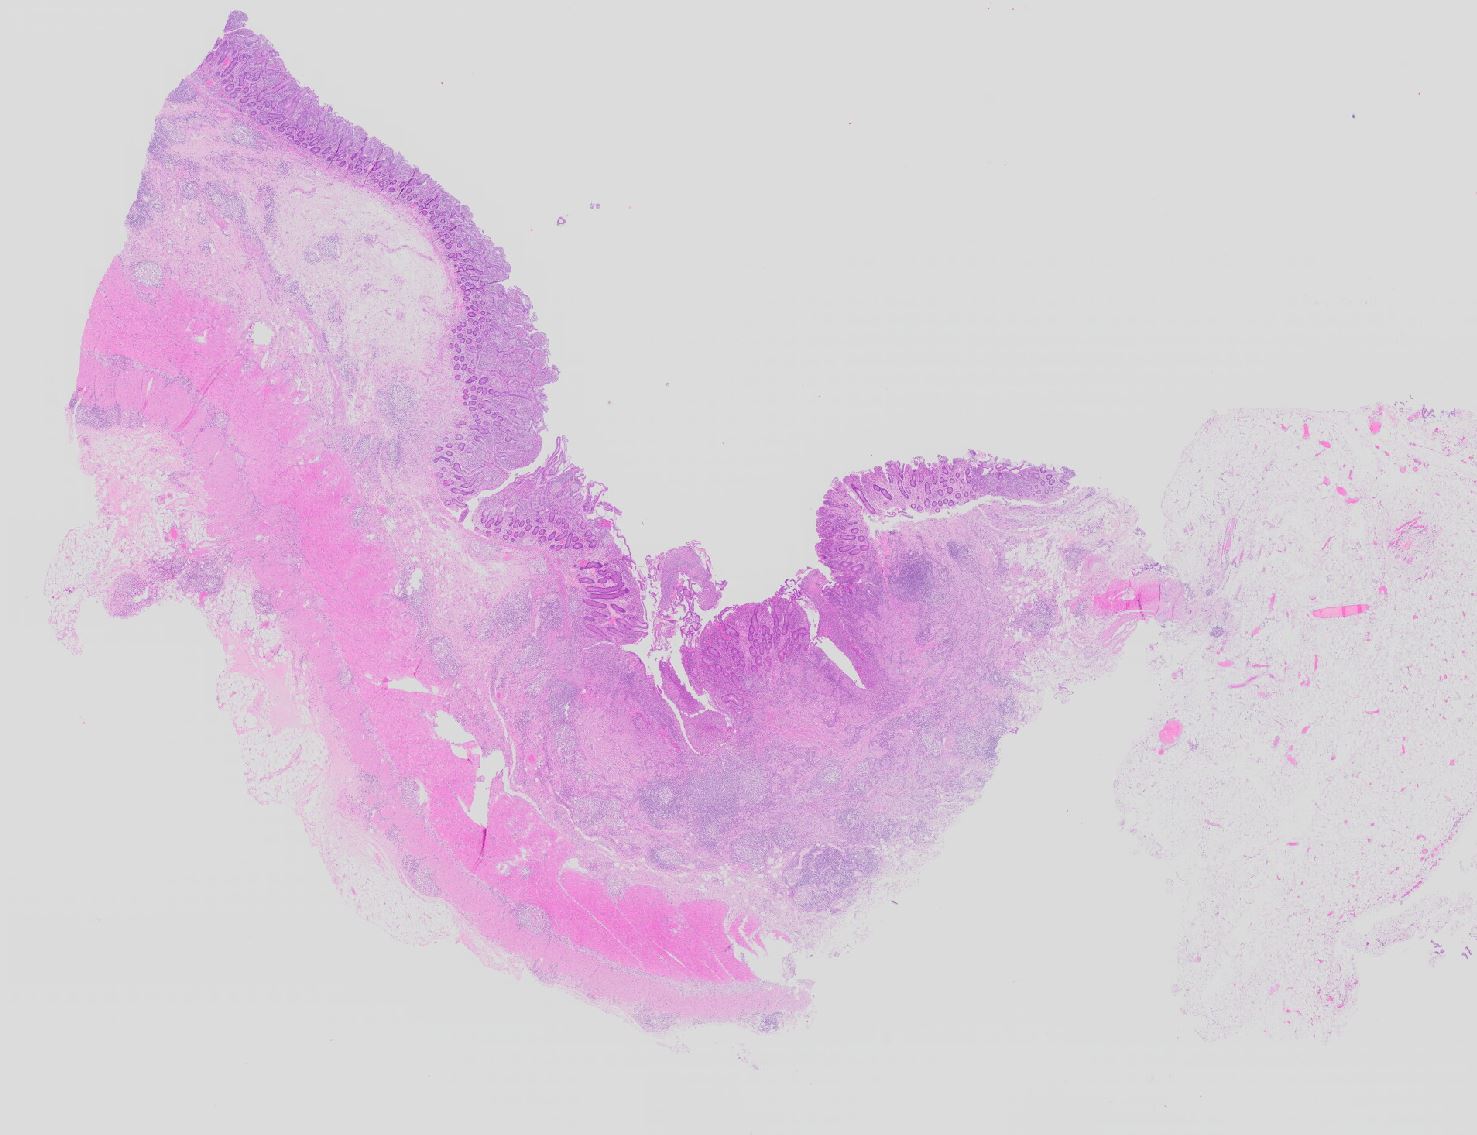

Die Verteilung der Läsionen im Darm ist sowohl makrokopisch (> 2884) als auch mikroskopisch (> 656) (> 409) diskontinuierlich und herdförmig ausgeprägt. Im Gegensatz zur Colitis ulcerosa können beim Morbus Crohn nicht nur das Kolon, sondern sämtliche Abschnitte des Gastrointestinaltraktes befallen sein. Am häufigsten ist das terminale Ileum zusammen mit dem Kolon befallen.

Makroskopisch typisch sind oberflächliche aphthöse Ulzera, gartenschlauchartige Strikturen im Dünn- und Dickdarm mit segmental verdickter und fibrosierter Darmwand, intramurale Abszesse, entzündliche Konglomerattumoren und verbackene Darmschlingen mit Fistelbildungen. Häufiger im Dünndarm als im Dickdarm findet sich das klassiche Pflastersteinrelief der Schleimhaut aufgrund rissförmiger Ulzera zwischen ödematösen Schleimhautarealen (> 369) Granulationsgewebspolypen oder Pseudopolypen (erhaltene Schleimhautinseln in Ulkusarealen) (> 408) finden sich beim Crohn seltener als bei der Colitis ulcerosa.

In Biopsien der Darmschleimhaut zeigen sich als Zeichen der Chronizität eine Architekturstörung, reepithelialisierte Schleimhautdefekte und metaplastische Veränderungen. Typisch für den Morbus Crohn sind entzündlich veränderte Schleimhautabschnitte neben weitgehend normaler Schleimhaut. In der Lamina propria findet sich ein verdichtetes gemischtes Infiltrat bestehend aus Lymphozyten, Plasmazellen, Makrophagen, neutrophilen und eosinophilen Granulozyten. Typisch für chronisch entzündliche Darmerkrankungen ist eine basal betonte Lymphoplasmozytose der Lamina propria. Die neutrophilen Granulozyten finden sich herdförmig in der Lamina propria, im Kryptenepithel (Kryptitis) und als Ansammlung in dilatierten Krypten (Kryptenabszess). Erhaltene Schleimhautabschnitte zwischen ulzerierten Arealen und Granulationsgewebe imponieren als entzündliche Pseudopolypen.

Befunde in der Mukosa wie epitheloidzellige Granulome, aphthöse Ulzera und Erosionen und fokal aktive Entzündung sind nicht spezifisch für den Morbus Crohn. Jene histologischen Aspekte, welche die Erkrankung am besten charakterisieren, sind in der Darmwand gelegen und lassen sich an einer endoskopisch gewonnenen Biopsie nicht nachweisen (fissurale, spaltförmige Ulzera, submukosales Ödem mit Lymphangiektasien, submukosale Fibrose, transmurale Entzündung mit lymphoidzelligen Aggregaten, neuromuskuläre Hypertrophie mit Wandverdickung (> 364), subseröse und submuköse Granulome (> 1133)).

• Architekturstörung: Verplumpung und Abflachung der Dünndarmzotten. Verzweigte Krypten.

• Transmurale Entzündungsinfiltrate mit Lymphfollikelbildung.

• Zahlreiche epitheloid-riesenzellige Granulome in allen Wandschichten.

• Schlitzförmige fissurale Ulzera mit Vernarbung der umgebenden Submukosa.

• Verdichtetes lymphoplasmazelluläres Entzündungsinfiltrat in der Lamina proria.